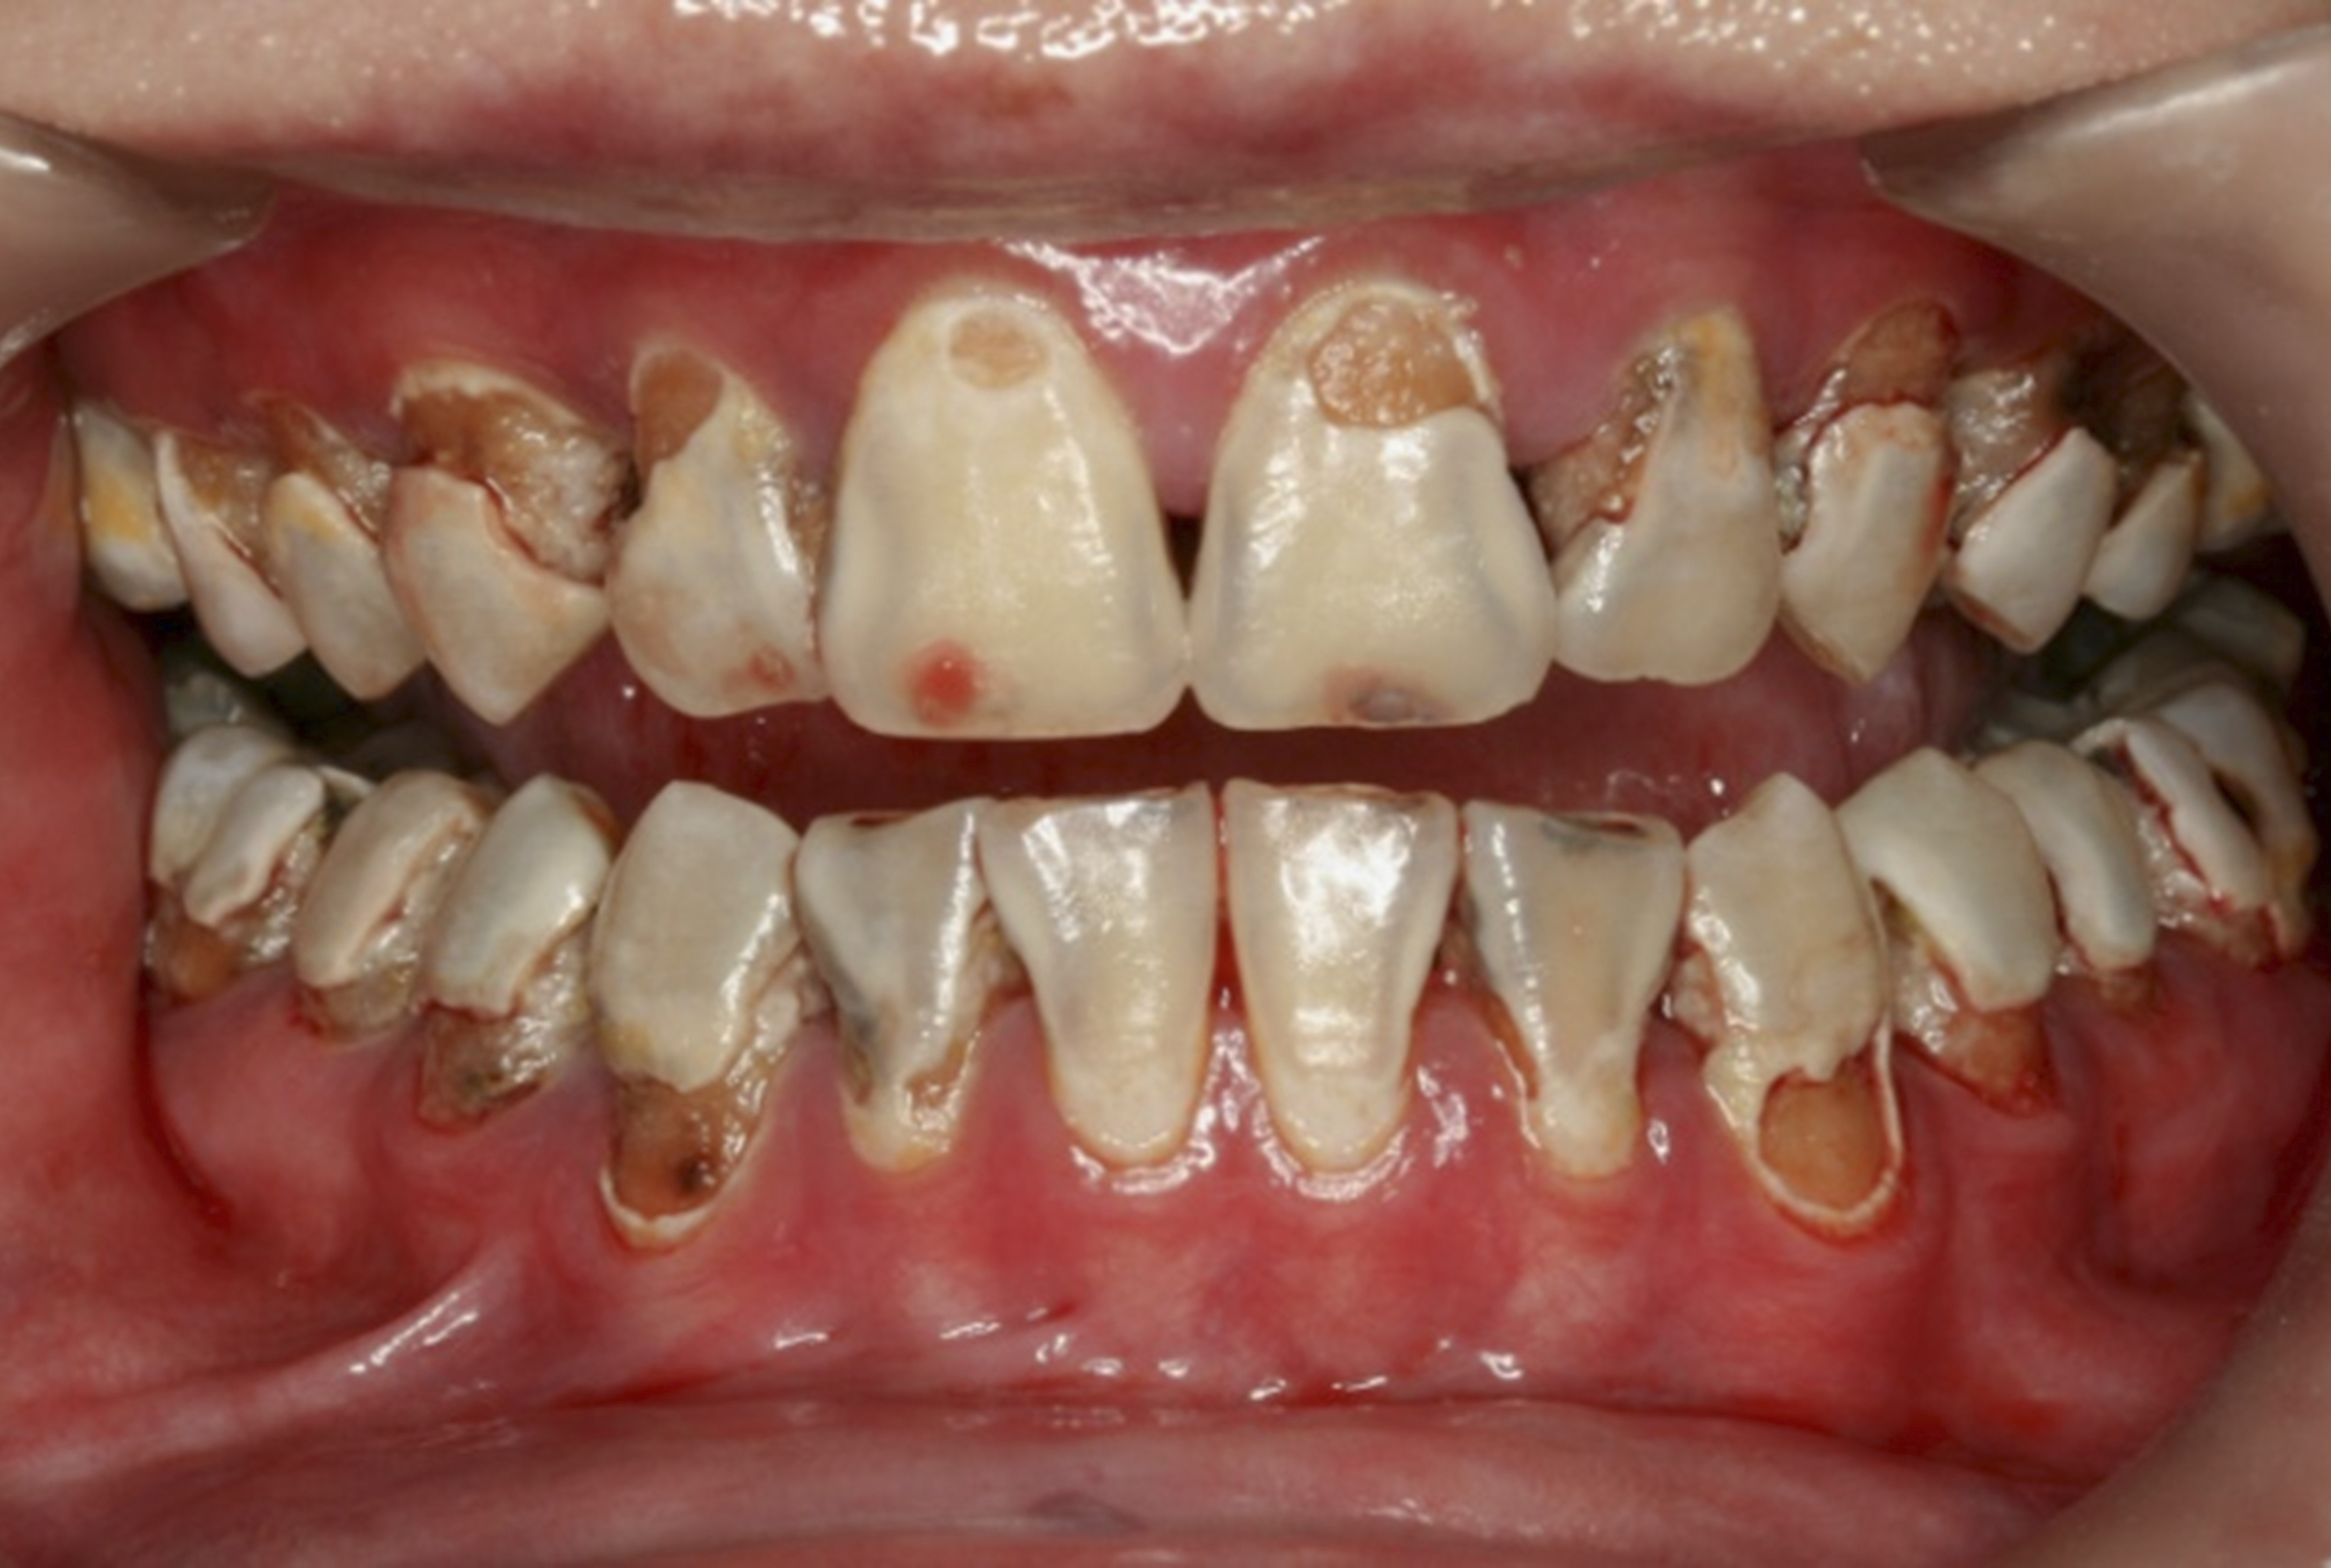

Fig 8. Use of 38% SDF to arrest rampant caries in a young teenager. Fig 8: Pre-treatment intraoral frontal view of rampant caries. Fig 9: Frontal view of arrested caries after consecutive application of SDF for 3 weeks. (images from Chu, et al, 201436 [reprinted with approval])

Fig 9. Use of 38% SDF to arrest rampant caries in a young teenager. Fig 8: Pre-treatment intraoral frontal view of rampant caries. Fig 9: Frontal view of arrested caries after consecutive application of SDF for 3 weeks. (images from Chu, et al, 201436 [reprinted with approval])

There is no consensus on the frequency of application, and 38% SDF has been used annually or biannually on clinical trials in children23,31,33,34 and in elderly.30,35 Yee and his co-worker found one-off application of 12% SDF was ineffective in arresting caries in children.31 The present authors applied 38% SDF weekly for 3 weeks to speed up the process of caries arrest and for treatment of rampant caries.36 One of the present authors’ case reports demonstrated that three weekly applications of 38% SDF can arrest rampant caries and relieve pain from hypersensitivity on a teenager. The SDF-treated caries were found arrested, and they turned coal black in appearance (Figure 9).